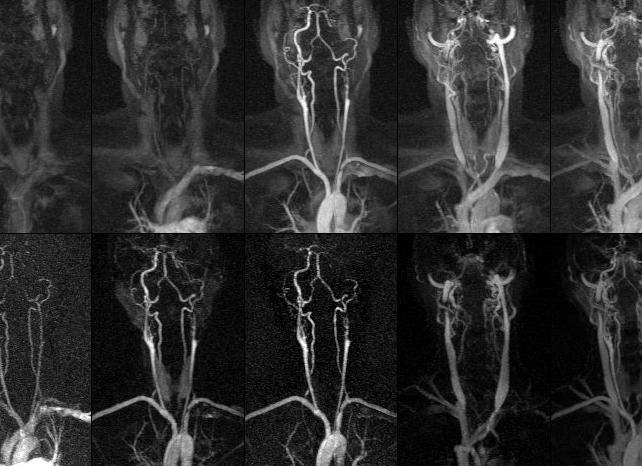

МРТ исследование является одним из самых современных методов изучения организма человека, которое широко используется при диагностике разных патологических состояний головного мозга. Благодаря ей можно увидеть любой орган послойно, а также очень точно оценить состояния структуры мягких тканей. Этот вид томографии является безопасным, качественным и высокоинформативным диагностическим исследованием.